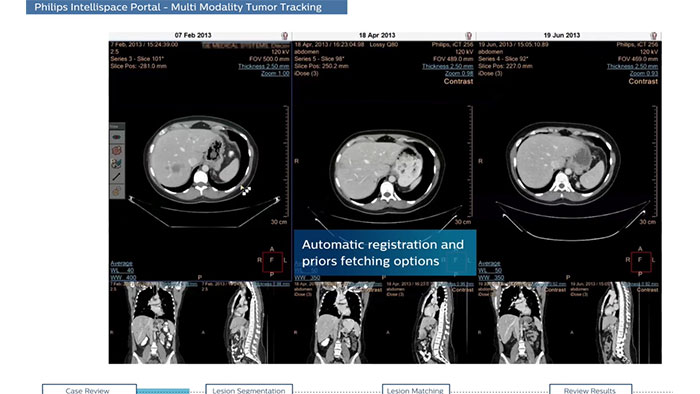

Streamlined workflow for follow up and analysis of oncology patients

MMTT is a post processing software used to display, process, analyze and quantify anatomical and functional images, for CT, MR, PET/CT, SPECT/CT and Dual Energy CT at one or multiple time points.

Semi-automatic tumor quantification

This semi-automated 3D (Volumetric) tumor response assessment tool, based on EASL (European Association for the Study of the Liver) criteria incorporates functional information from contrast-enhanced scans.